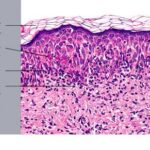

Histopathology. EM is considered the prototype of the vacuolar form of interface dermatitis . The early changes include vacuolization of the basal cell layer; tagging of lymphocytes along the dermal-epidermal junction; and a sparse, superficial, perivascular lymphoid infiltrate . Necrosis of individual keratinocytes in the basal unit occurs, which is the hallmark of EM. Because of its acute nature, there is an orthokeratotic stratum corneum. Mild spongiosis, papillary dermal edema, and extravasation of red blood cells are seen. As the lesion becomes more developed, there is a moderate lichenoid infiltrate of Iymphohistiocytes at the dermal-epidermal junction with exocytosis. More apoptotic keratinocytes within and above the basal epidermal layer are present. The |

intensity of epidermal necrosis varies from vacuolated individual keratinocytes surrounded by lymphocytes (satellite cell necrosis) at the basal unit to confluent necrosis in association with intraepidermal and subepidermal vesicles. The dermal infiltrate comprises lymphocytes and histiocytes. Eosinophils may also be present. Although one study has noted a significant number of eosinophils in drug-induced EM, this has not been noted by others. In the authors’ estimation, a generous number of eosinophils exclude EM. One study has found that an acrosyringium concentration of apoptotic keratinocytes in EM is a clue to a drug etiology . In early lesions of SJSITEN, apoptotic keratinocytes are observed scattered in the basal layer of the epidermis. In established lesions, there are numerous necrotic keratinocytes, even full-thickness epidermal necrosis, and a subepidermal bulla. The dermal inflammatory infiltrate is sparser in TEN than in EM (Fig. 9-278). Extravasated erythrocytes are commonly found within the blister cavity. Melanophages within the papillary dermis occur in late lesions. Eccrine epithelium shows a variety of changes from basal cell apoptosis to necrosis of the duct. |

In general, EM shows less epidermal necrosis, more dermal inflammation, and exocytosis, whereas SJS and TEN reveal more epidermal necrosis, less dermal inflammation, and exocytosis. However, due to the overlapping histologic features among EM, SJS, and TEN, histologic examination-while important for recognizing the spectrum of disorders-is not reliable for classifying the disease. Correlation with clinical presentation is essential. |